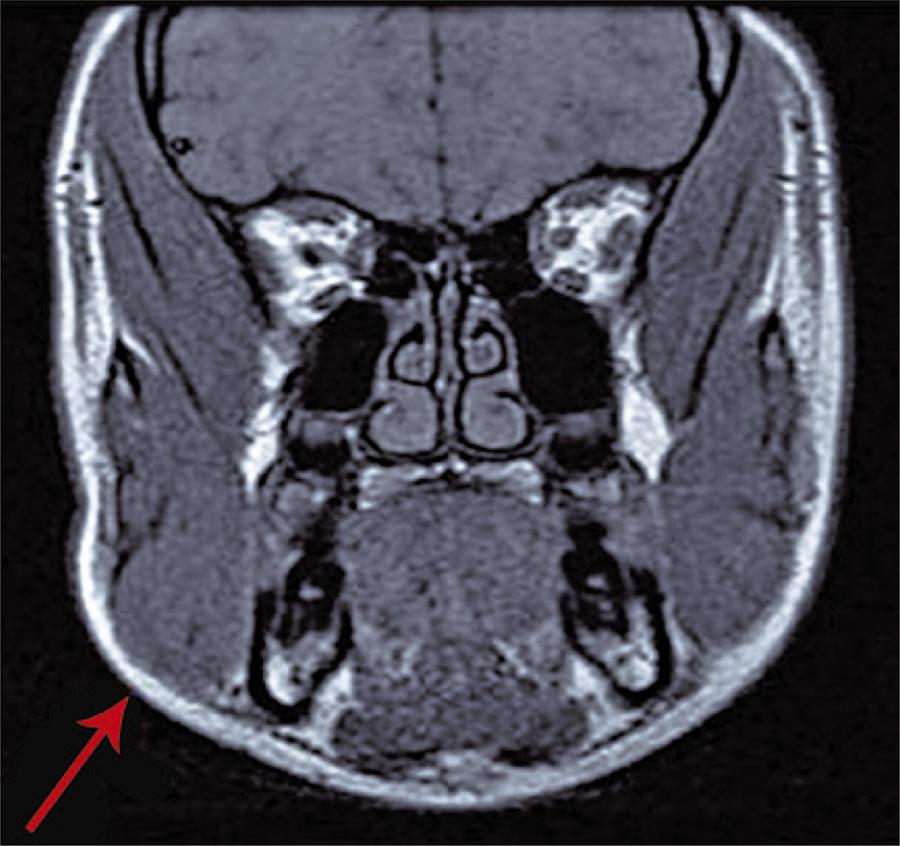

Apresenta-se o caso de uma adolescente, 15 anos, sexo feminino, com antecedentes pessoais irrelevantes, observada no Serviço de Urgência por tumefação mandibular direita, indolor, com 3 meses de evolução e agravamento progressivo. Sem história prévia de traumatismo facial, trismus, sintomas constitucionais ou doença periodontal. À observação (), apresentava assimetria facial, com tumefação no ângulo mandibular direito, mais evidente com oclusão mandibular, palpando-se massa de 4cm de maior eixo, indolor, consistência elástica, com área sobreposta de maior consistência, de 2cm de diâmetro e aderente ao osso. Avaliação analítica sem alterações, com parâmetros inflamatórios e serologias virais negativas. Sem alterações detectáveis em ecografia das glândulas salivares, tendo realizado ressonância magnética da face () que demonstrava assimetria facial envolvendo o músculo masseter e glândula parótida direitos, sem patologia intrínseca, consistente com hipertrofia do masseter. A adolescente foi encaminhada para consulta de cirurgia pediátrica, para eventual cirurgia estética.